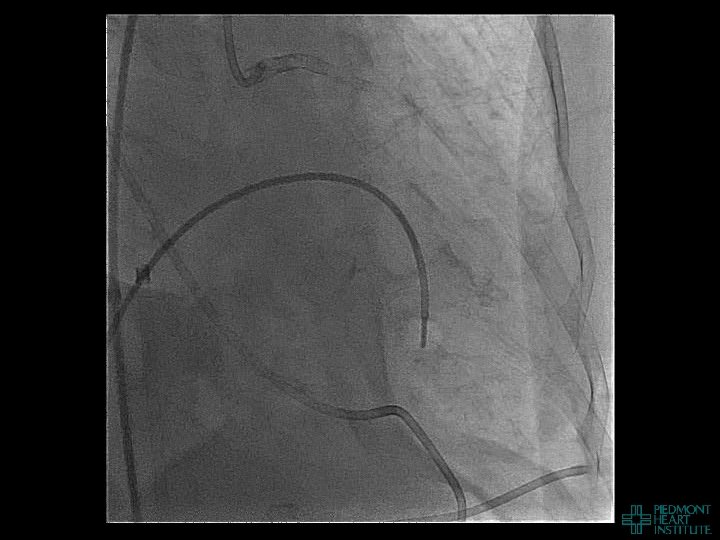

Coronary Perforation Methods of Patient Management • Dual Catheter (‘Ping Pong’) Technique • Prolonged

Coronary Perforation Methods of Patient Management • Dual Catheter (‘Ping Pong’) Technique • Prolonged balloon inflation and covered stents • Reversal of anticoagulation — Know contradictions to protamine sulfate for UFH; Avoid bivalirudin, LMWH — Reserve GP 2 b 3 a inhibition until successful crossing and wire change-out Embolization • — Coil, gelfoam, methacrylate, autologous blood/fat • Microcatheter Occlusion • Confirmation of successful management — Contralateral injection — Right heart catheterization — Echocardiogram — Contrast echocardiography